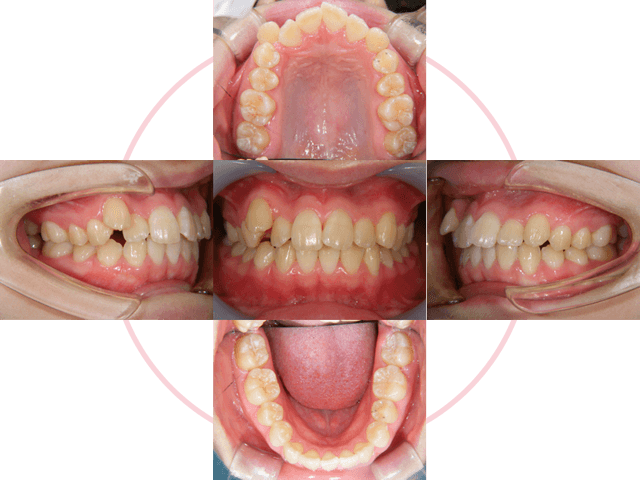

治療後

治療前

1年半の矯正治療で人生が変わることもあります。口元、笑顔の印象はそれだけインパクト大です。